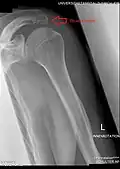

Left scapula, posterior view. Acromion shown in red.

Skeleton, posterior view. Acromion of each scapula shown in red.